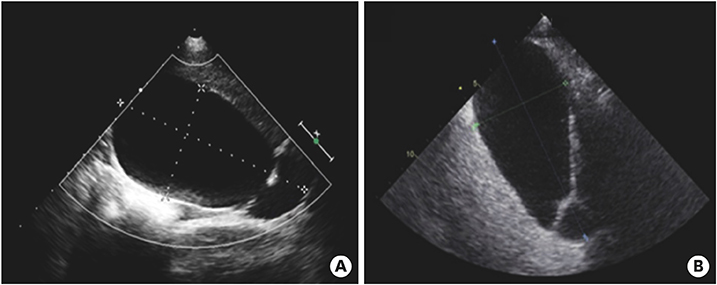

Fig. 4

Abdominal computed tomography (A, B) performed at 10 days after fever onset showed marked distended gallbladder (8.0×5.5 cm in size) without wall thickening or sludge, which is consistent with gallbladder hydrops.